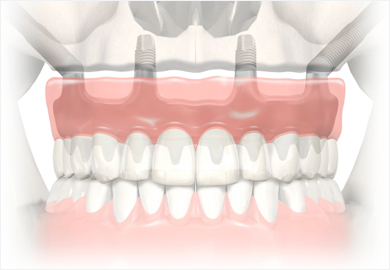

Zahnersatz (implantatgetragene Brücke)

Nicht immer ist es notwendig, jeden fehlenden Zahn mit einem eigenen Implantat zu ersetzen. Es gibt sowohl solche Brücken, die auf Zahnimplantaten aufgebaut, als auch solche, die von natürlichen Zähnen getragen werden.

Es ist z. B. möglich, eine Brücke für drei Zähne auf zwei Implantaten aufzubauen, oder eine Brücke für zwölf Zähne von acht Implantaten tragen zu lassen.